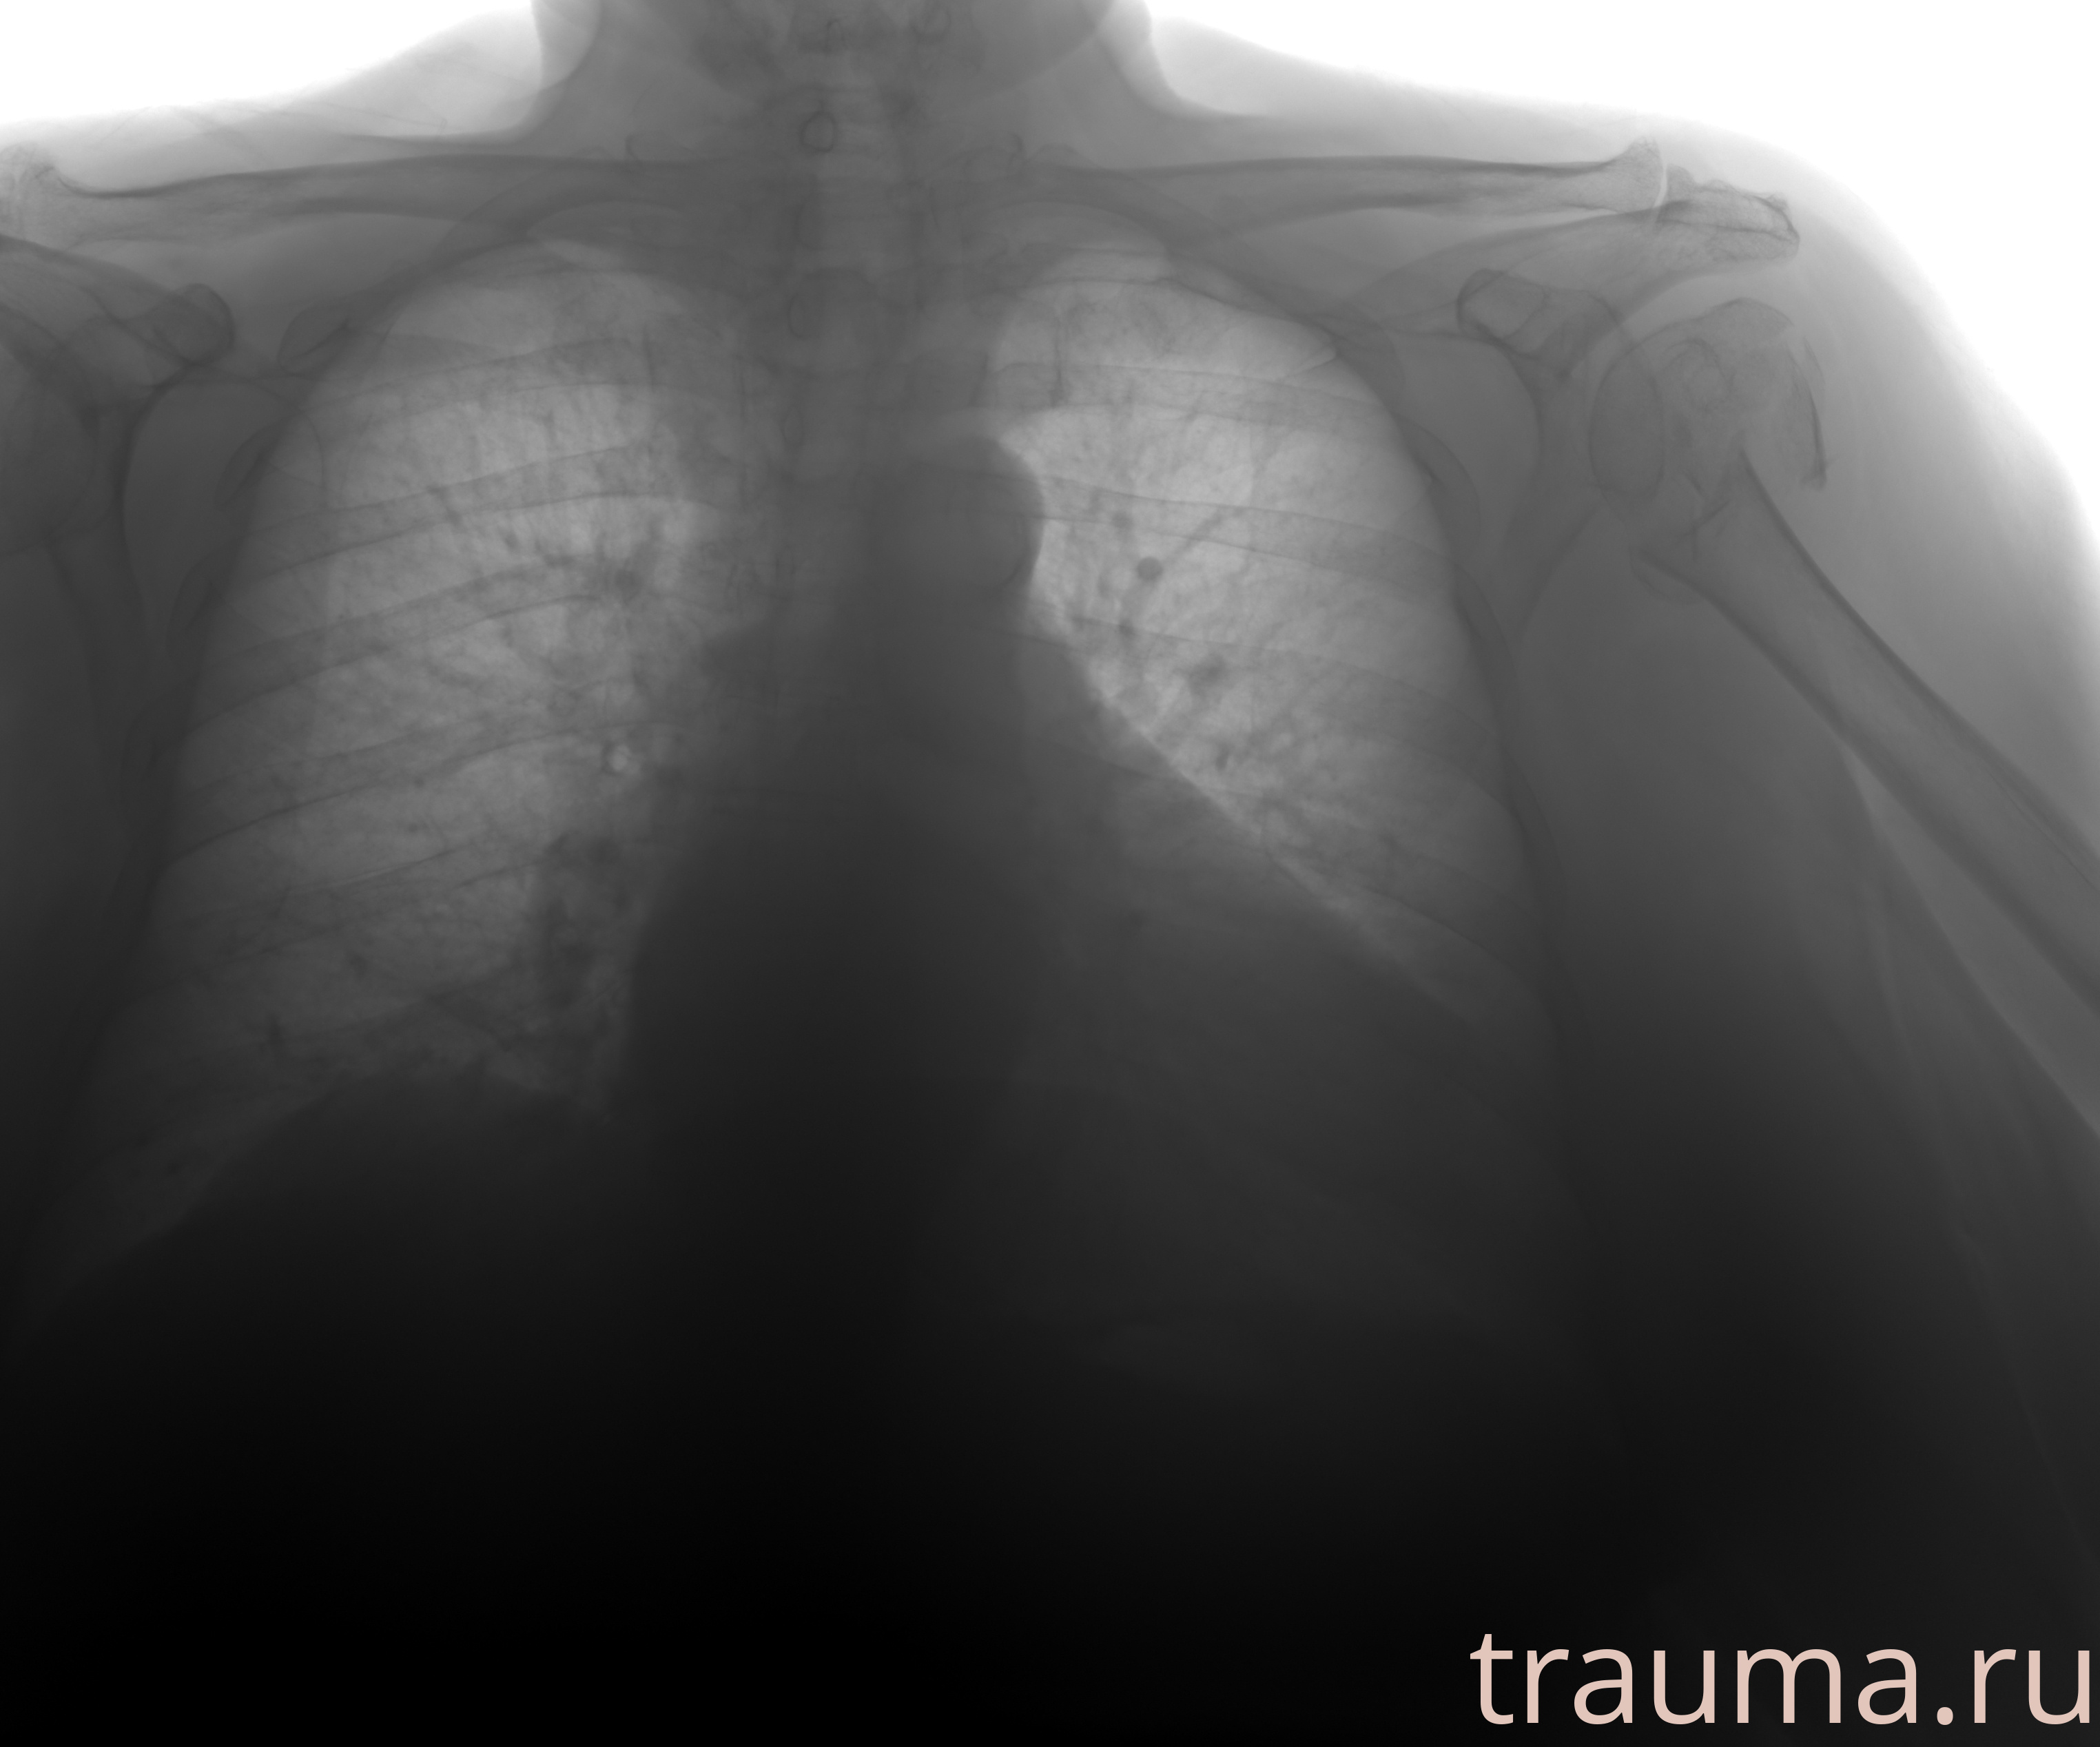

Рентген на дому: по вашему адресу приезжает врач-рентгенолог, травматолог-ортопед с мобильным рентгеновским аппаратом, проводит диагностику травмы или заболевания, делает необходимые рентгенограммы, дает рекомендации по дальнейшему лечению. Получить качественные снимки в домашних условиях возможно благодаря уникальной методике, разработанной МосРентген Центром для института  Склифосовского

при переломе шейки бедра и пневмонии от компании МосРентген Центр - партнера Института имени Склифосовского